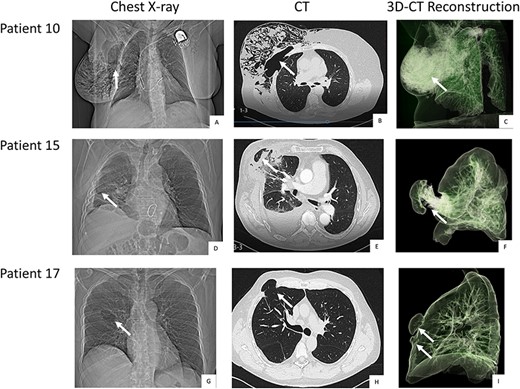

The initial diagnostic step of lung herniation involves clinical examination of the patient and palpation while coughing to identify herniation on the right thoracic wall. Further diagnostic measures include a chest X-ray and thoracic computed tomography (CT) scan, with the latter being the diagnostic tool of choice. Thoracic CT should be performed in women with unspecific symptoms either to exclude or provide evidence of lung herniation. Even if a protrusion in the area of the chest wall is observed during coughing, a thoracic CT is essential for diagnosis and for surgical planning. CT scans help to identify the exact area where chest wall reconstruction is necessary and to detect or exclude the presence of a double pulmonary hernia involving two intercostal spaces (Fig. 1).

Pre-operative chest-X-ray, CT and thoracic CT reconstruction of patient 10 (A, B, C), 15 (D, E, F) and 17 (G, H, I). Legend: The white arrows point at the herniation. Patient 10 and 15 come with a single hernia. Patient 17 was diagnosed with double herniation.

Only a few patients are symptomatic shortly after the MICS procedure. A protrusion on the right thoracic side that is visible when coughing often first presents in the months following the primary operation. This symptom is easier to diagnose in male patients than in female patients. Patient complaints regarding respiratory pain and discomfort post MICS should be taken seriously and followed up with a chest CT (Fig. 1).